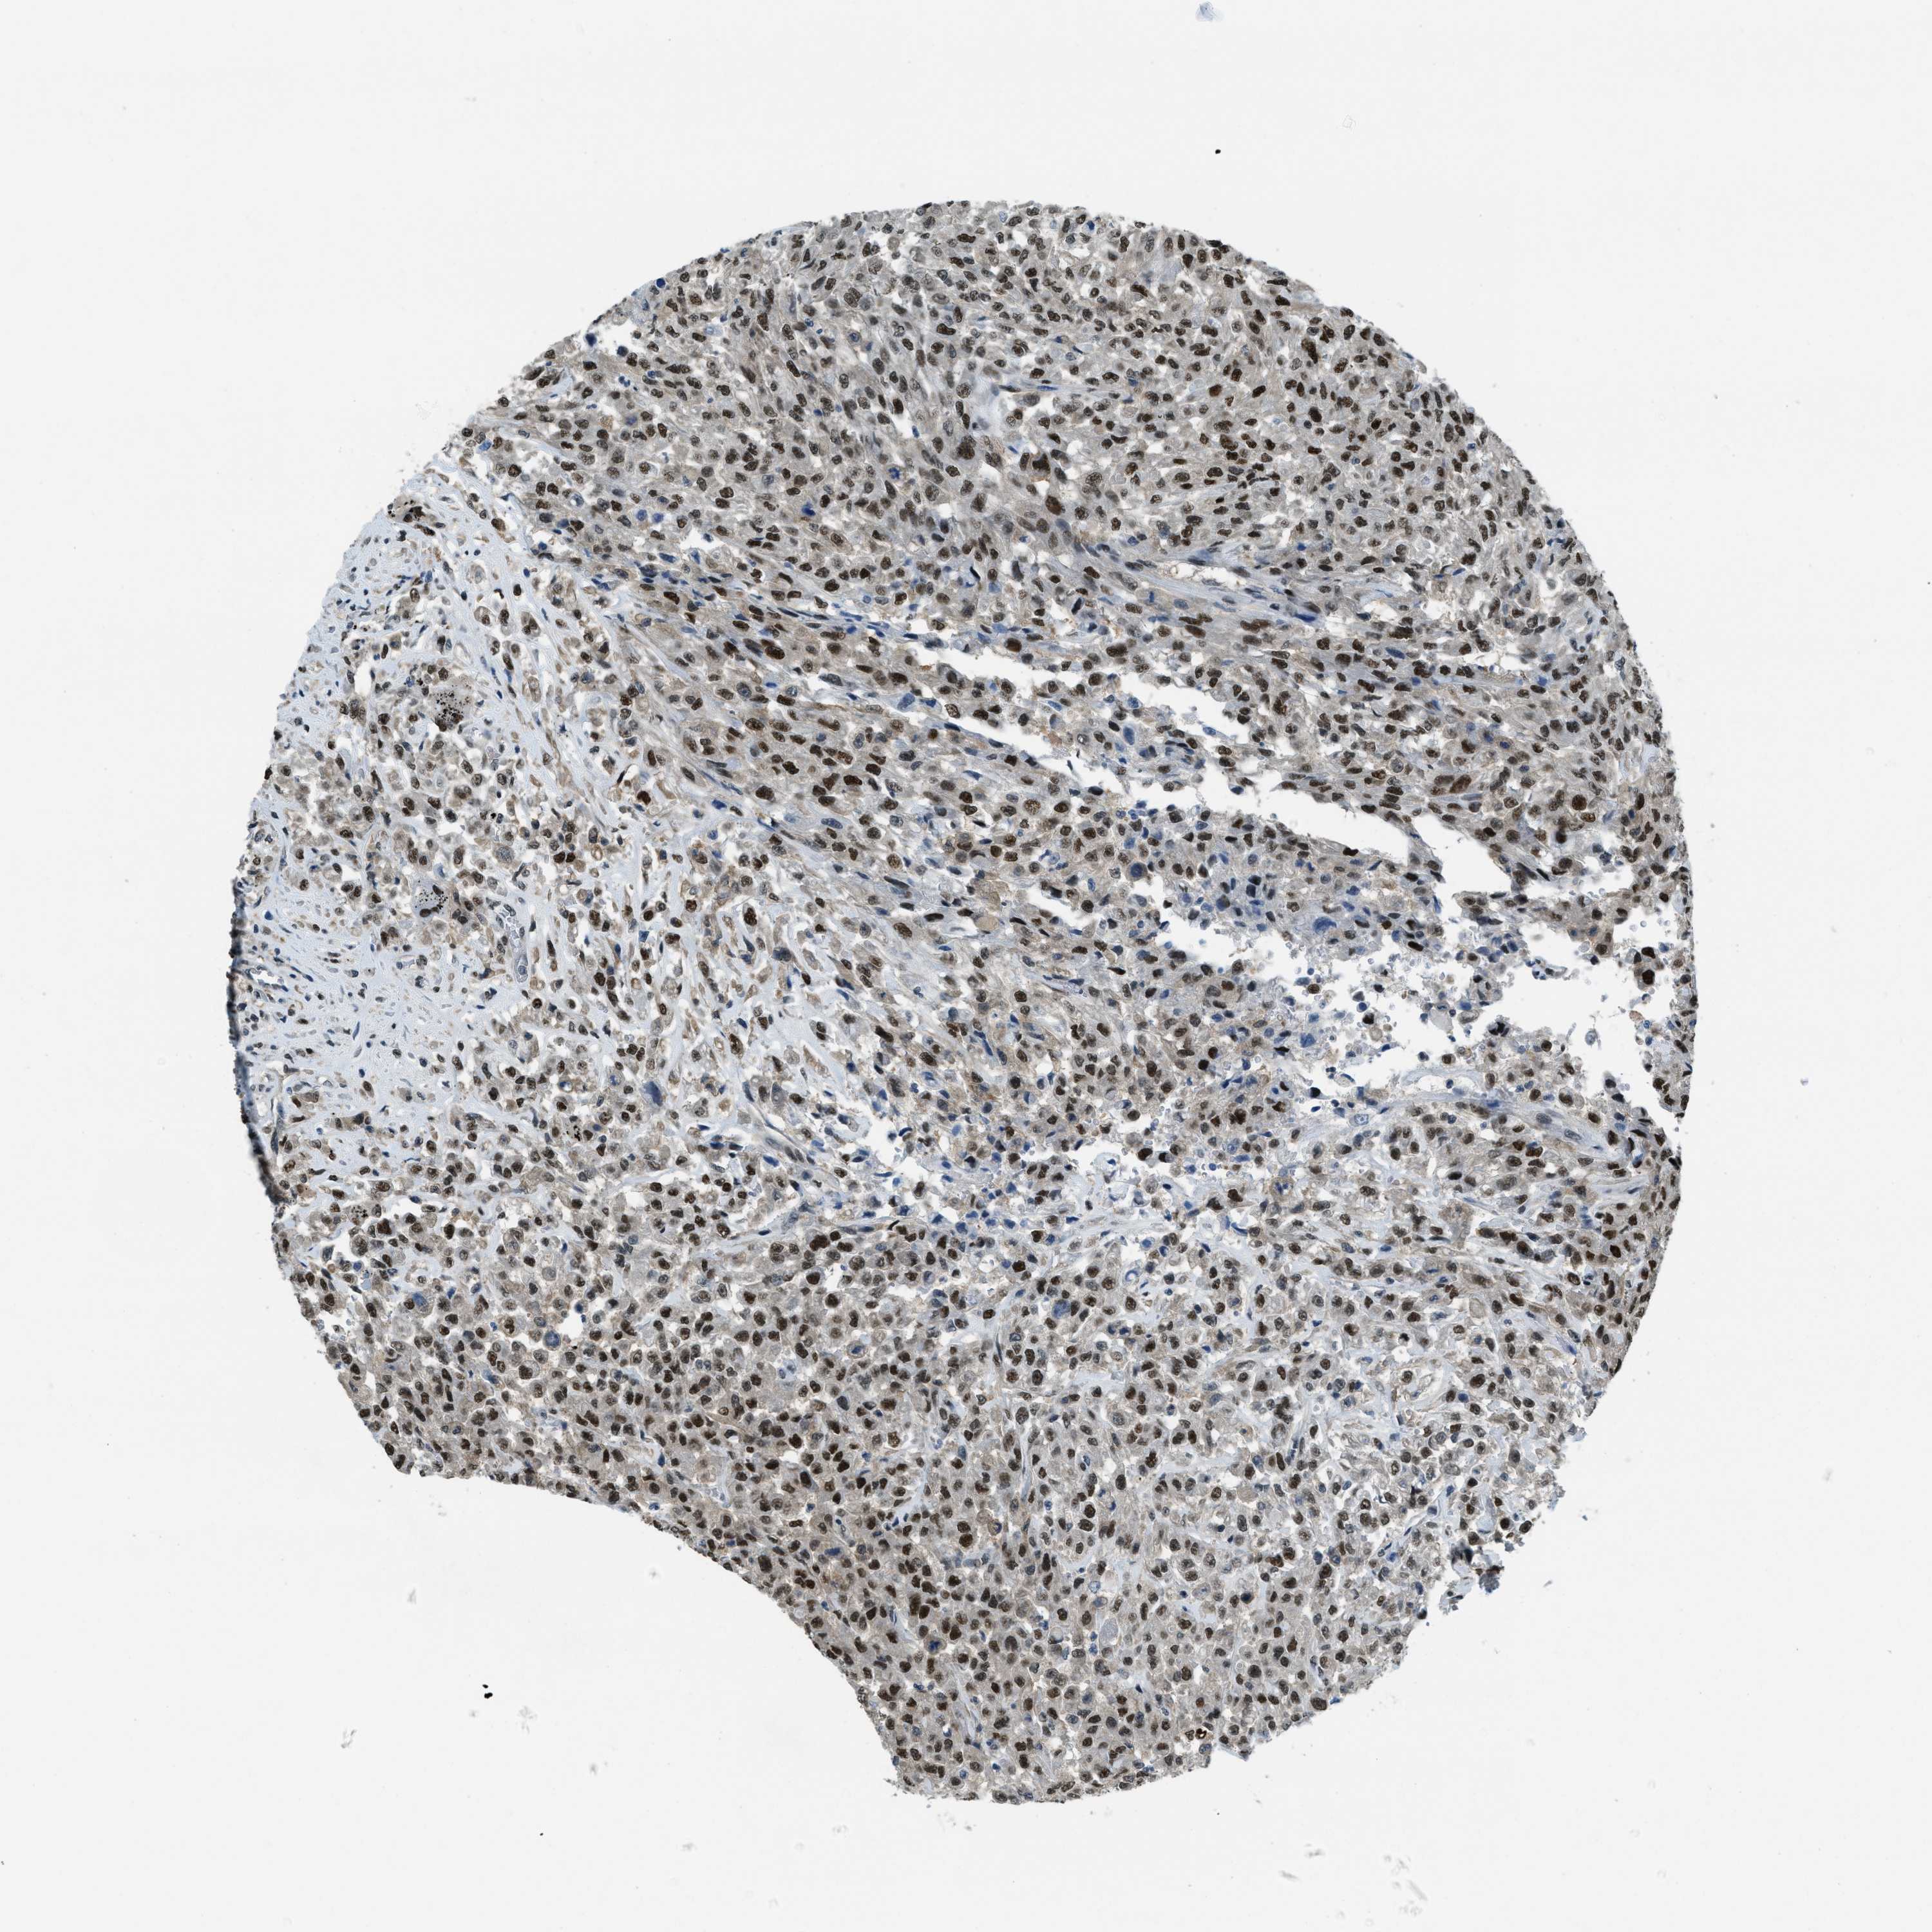

UROTHELIAL CANCER - Protein expressioni

A mouse-over function shows sample information and annotation data. Click on an image to view it in a full screen mode. Samples can be filtered based on level of antibody staining by selecting one or several of the following categories: high, medium, low and not detected. The assay and annotation is described here.

Note that samples used for immunohistochemistry by the Human Protein Atlas do not correspond to samples in the TCGA dataset.

Antibody stainingi

Antibody staining in the annotated cell types in the current human tissue is reported as not detected, low, medium, or high, based on conventional immunohistochemistry profiling in selected tissues. This score is based on the combination of the staining intensity and fraction of stained cells.

Each image is clickable and will lead to virtual microscopy that enables deeper exploration of all samples and also displays staining intensity scores, fraction scores and subcellular localization as well as patient and tissue information for each sample.

Antibody HPA017899

Staining

High

Medium

Low

Not detected

Intensity

Strong

Moderate

Weak

Negative

Quantity

>75%

75%-25%

<25%

None

Location

Urothelial carcinoma, Low grade

Urothelial carcinoma, High grade